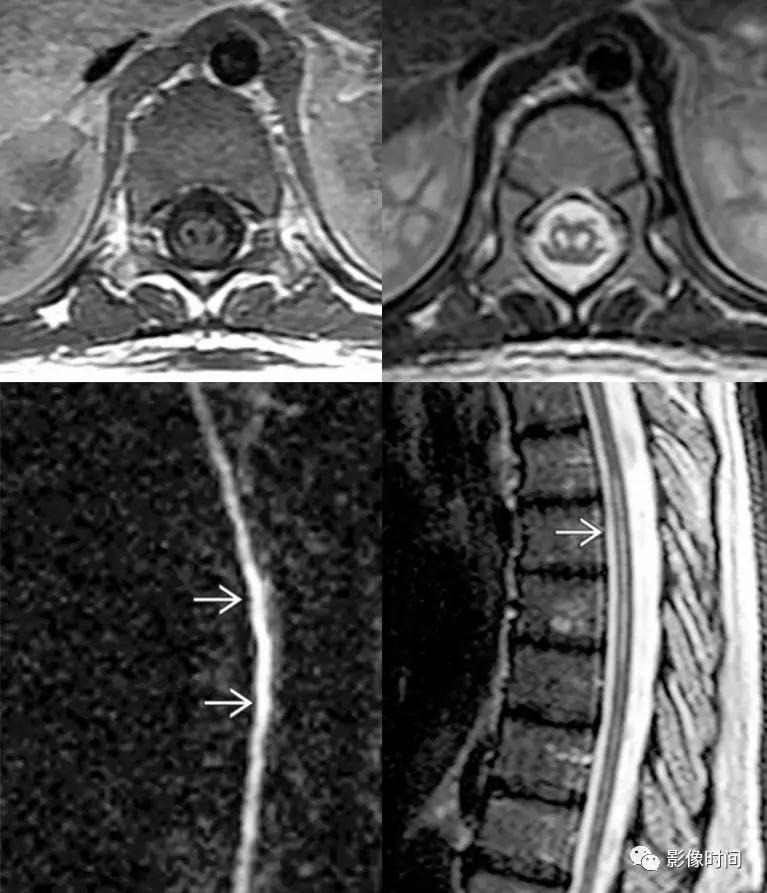

脊髓梗死(spinal infarction),各种原因(比如动脉夹层、椎体术后、纤维软骨栓塞等等)导致的脊髓供血动脉缺血,脊髓前动脉最多见

MRI:

-

前 2/3 脊髓(脊髓前动脉);双侧灰质前角(脊髓前动脉);后索(脊髓后动脉)

T2WI 高信号病灶,DWI 呈高信号,ADC 呈低信号

轴位「鹰眼征」

矢状位「铅笔征」

脊髓前动脉梗死导致双侧灰质前角梗死(鹰眼征),矢状位呈线样,DWI 提示细胞毒性水肿

脊髓前动脉梗死导致脊髓前 2/3 梗死,DWI 提示细胞毒性水肿

脊髓后动脉梗死导致脊髓后索梗死,DWI 提示细胞毒性水肿

Sulcal 动脉梗死